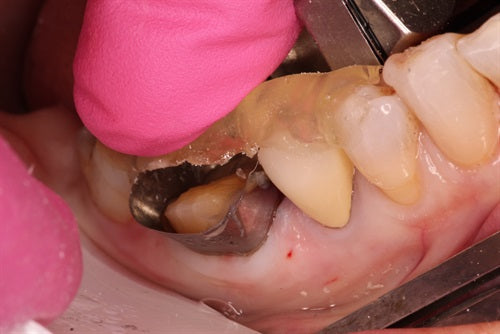

Recurrent caries under crown - "Thinking outside of the box" by Dr. Ahmad Fayad

Introduction: This case was completed by Dr. Ahmad Fayad of Lessard Dental located in Alberta, Canada. Food impaction area that caused massive carious lesion at the distal of the lower... Read More